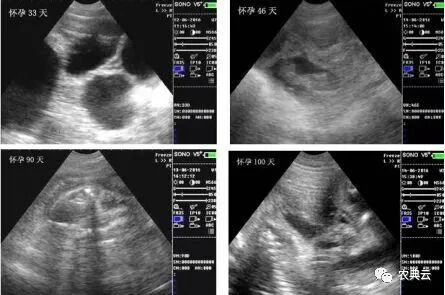

1. 第一时间检测出是否怀孕(第一个发情期之后,一般在24-29天)应该讲在这个阶段检测出有无怀孕,对于养殖场来说是最省钱的,如果空怀可以及时再配,从而大大缩短了无效饲养的时间。早期估测出来胚胎个数,有利于妊娠母猪日粮中营养配方以及饲喂量的调整。当胚胎个数较多而营养和日粮跟不上时,容易造成流产或弱胎;而当胚胎个数较少而营养和日粮过剩时,容易造成胚胎个体发育过大,引起难产。